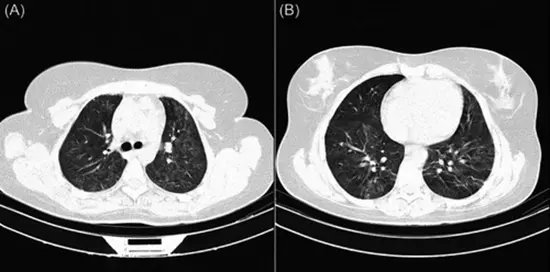

Correlation of clinical, laboratory, and short-term outcomes of immunocompromised and immunocompetent COVID-19 patients with semi-quantitative chest CT score findings: A case-control study

✔️ Development and optimization of lung imaging protocols for faster and more accurate COVID-19 diagnosis